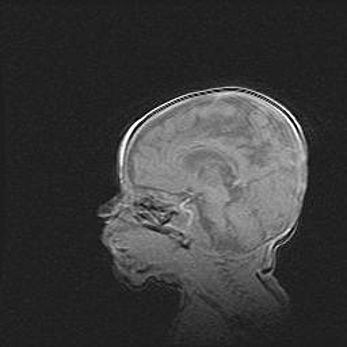

Аномалия Денди-Уокера. Признаки гипоплазии мозолистого тела.

Возраст: 5 месяцев 3 дня

Вес: 5550 г

Пол: мужской

Окружность головы: 39 см

Срок гестации: 40 недель

Аномалия Денди-Уокера – это порок развития головного мозга, для которого характерна триада симптомов: гипотрофия или аплазия червя мозжечка и/или полушарий мозжечка, расширение четвёртого желудочка с формированием ликворной кисты задней черепной ямки, гипертензионная гидроцефалия различной степени.

Гипоплазия мозолистого тела относится к дефектам внутриутробного этапа развития мозговой ткани, возникающим в процессе закладки структур головного мозга, что происходит на начальных этапах развития эмбриона.